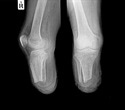

For initial diagnosis, physical examination of the foot is performed to analyze the foot mechanics. If the pain is severe, doctors may recommend imaging tests, such as x-ray, CT scan, MRI, or ultrasound, to detect the nature and degree of deformity.